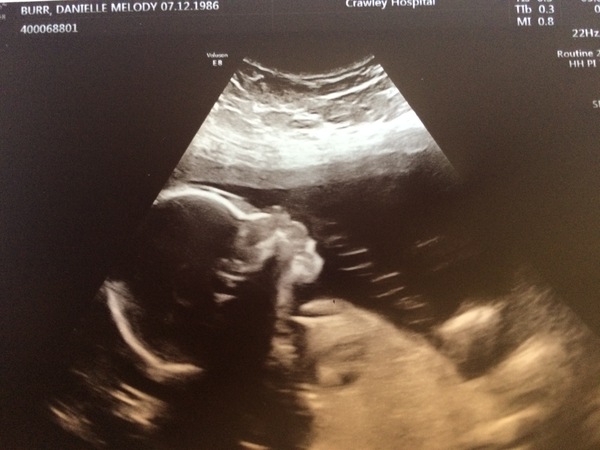

MrsB12345 · 16/06/2017 21:46

We had our 20 week scan today. Baby didn't want to lie in the right position so we didn't get to find out the sex and need to go back in 2 weeks as they didn't get to see enough of the heart, spine and umbilical chord so we get another scan. Woohoo

Bumdishcloths · 16/06/2017 21:49

Awww, good photo Grin